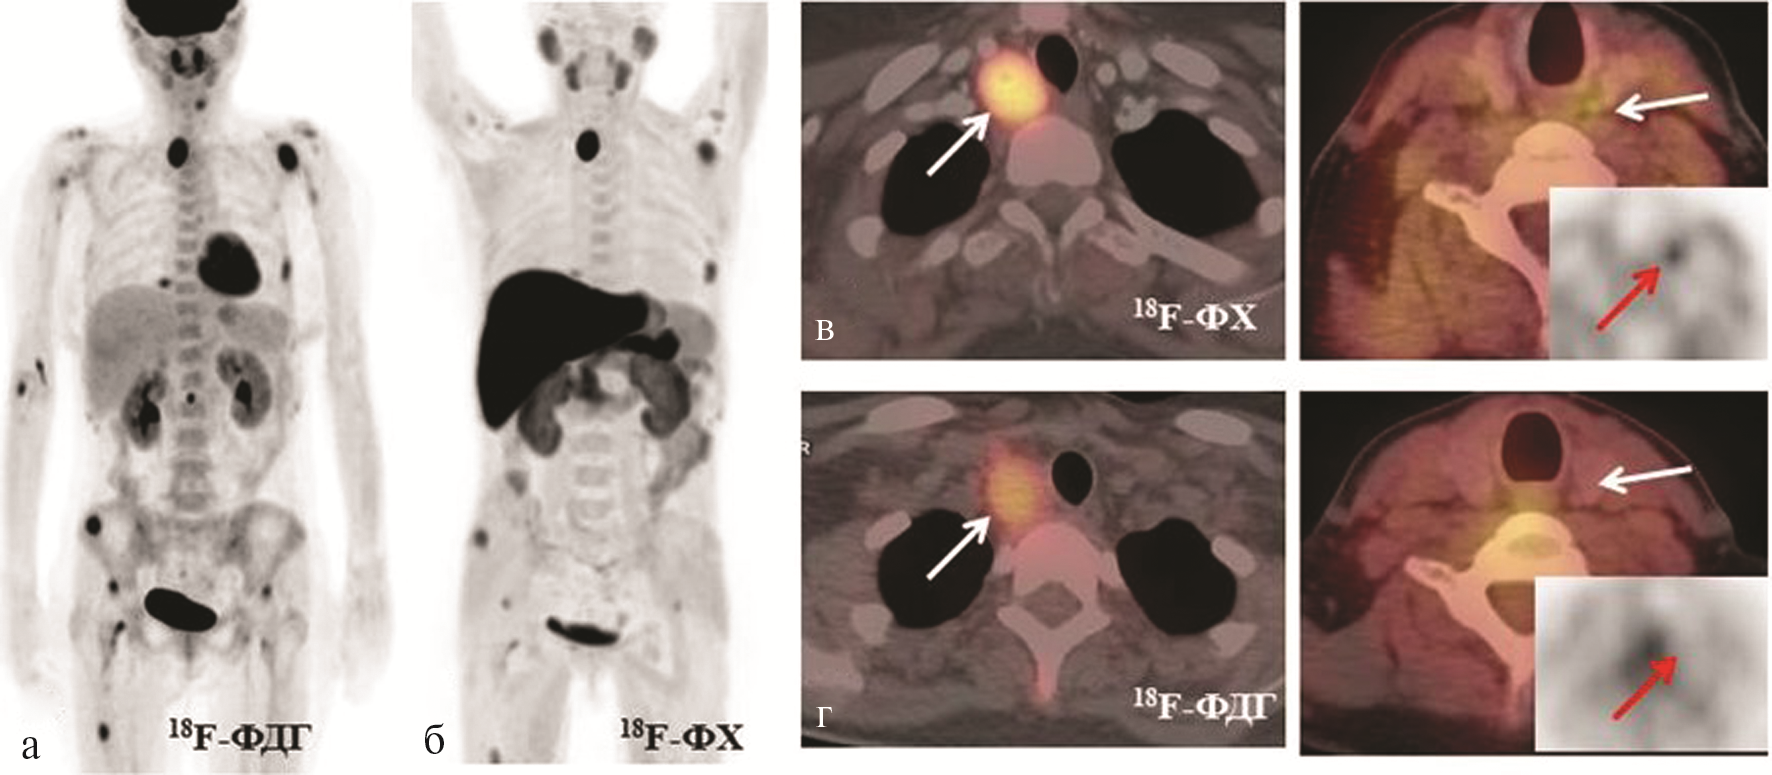

При УЗИ выявлены объемные образования в правой нижней ОЩЖ (30×20×18 мм) и левой верхней ОЩЖ (12×04×04 мм) с четкими контурами, пониженной эхогенности; регионарные лимфоузлы не увеличены, не изменены. При сцинтиграфии ОЩЖ с 99mTc-МИБИ определяется накопление РФП в проекции правой нижней ОЩЖ (размером 20×10 мм). При остеоденситомерии выявлено выраженное снижение минеральной плотности костной ткани (МПК) максимально до –5,1 SD в лучевой кости по Z-крите рию. Учитывая данные лабораторно-инструментального обследования и результаты нашего предыдущего исследования [20], у пациентки была заподозрена карцинома ОЩЖ. Для оценки распространенности процесса и исключения метастазов больная была направлена в ФГБУ «НМИЦ онкологии им. Н.Н. Блохина» для проведения ПЭТ/КТ с 18F-ФДГ (рис. 1, а, на цв. вклейке). Дополнительно было решено провести ПЭТ с 18F-ФХ (см. рис. 1, б, на цв. вклейке), исследования проводилсь в разные дни. При исследовании с 18F-ФХ выявлены объемные образования с очаговым накоплением РФП: в правой нижней ОЩЖ размером 24×23×32 мм (макс. SUV 17,09), в левой верхней ОЩЖ размером 7×5 мм (макс. SUV 2,74) (см. рис. 1, в, на цв. вклейке). При исследовании с 18F-ФДГ метаболическая активность в образовании правой ОЩЖ была ниже (макс. SUV 9,95), в левой верхней ОЩЖ повышенного накопления 18F-ФДГ не обнаружено (см. рис. 1, г, на цв. вклейке).

Рис. 1. Результаты лучевой диагностики пациентки В.

а — ПЭТ с 18F-ФДГ (проекция максимальной интенсивности); б — ПЭТ с 18F-ФХ (проекция максимальной интенсивности);

в — ПЭТ/КТ с 18F-ФХ (аксиальные срезы — стрелками указаны очаги в правой нижней и левой верхней ОЩЖ); г — ПЭТ/КТ с 18F-ФДГ (аксиальные срезы — стрелками указаны ОЩЖ, в правой с накоплением, в левой без накопления РФП).

Выявлены множественные очаги патологического накопления обоих РФП в костях, которые соответствовали по КТ разнокалиберным очагам литической деструкции, с замещением нормальной костной ткани патологической, с деструкцией кортикальных слоев («бурые опухоли») и участкам уплотнения (фиброз) костного мозга в длинных трубчатых костях. Накопление 18F-ФДГ и 18F-ФХ во всех костных очагах было примерно одинаковым (макс. SUV от 2,74 до 6,55). Для демонстрации мы выбрали два очага — в акромиальном отростке левой лопатки и средней трети левой бедренной кости (рис. 2, на цв. вклейке).